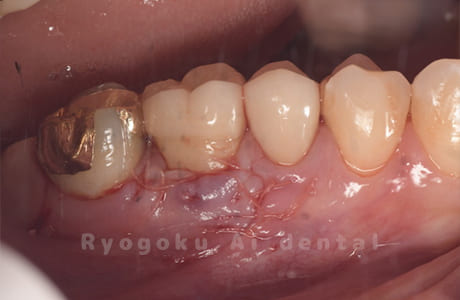

Case08

-

- 原因

- 歯根嚢胞、重度カリエス

- 治療内容

- 再植手術、クラウンレングスニング

- 治療費用

- ¥99,000

他院で根管治療を行ったが、なかなか治らず、抜歯を宣告されたとのことでご来院された患者様です。歯がかなり削られており、また、歯根の根尖部の病変が大きく、嚢胞化しているため、クラウンレングスニングと再植歯根端手術を同時に行いました。違和感もなくなり、大変満足されています。

<リスク・副作用>

外科手術のため、術後に出血、痛みや腫れ、違和感を伴います。口腔内の状態によっては適応できないことがあります。歯根端切除で治らなければ抜歯を検討しなくていけない場合もあります。